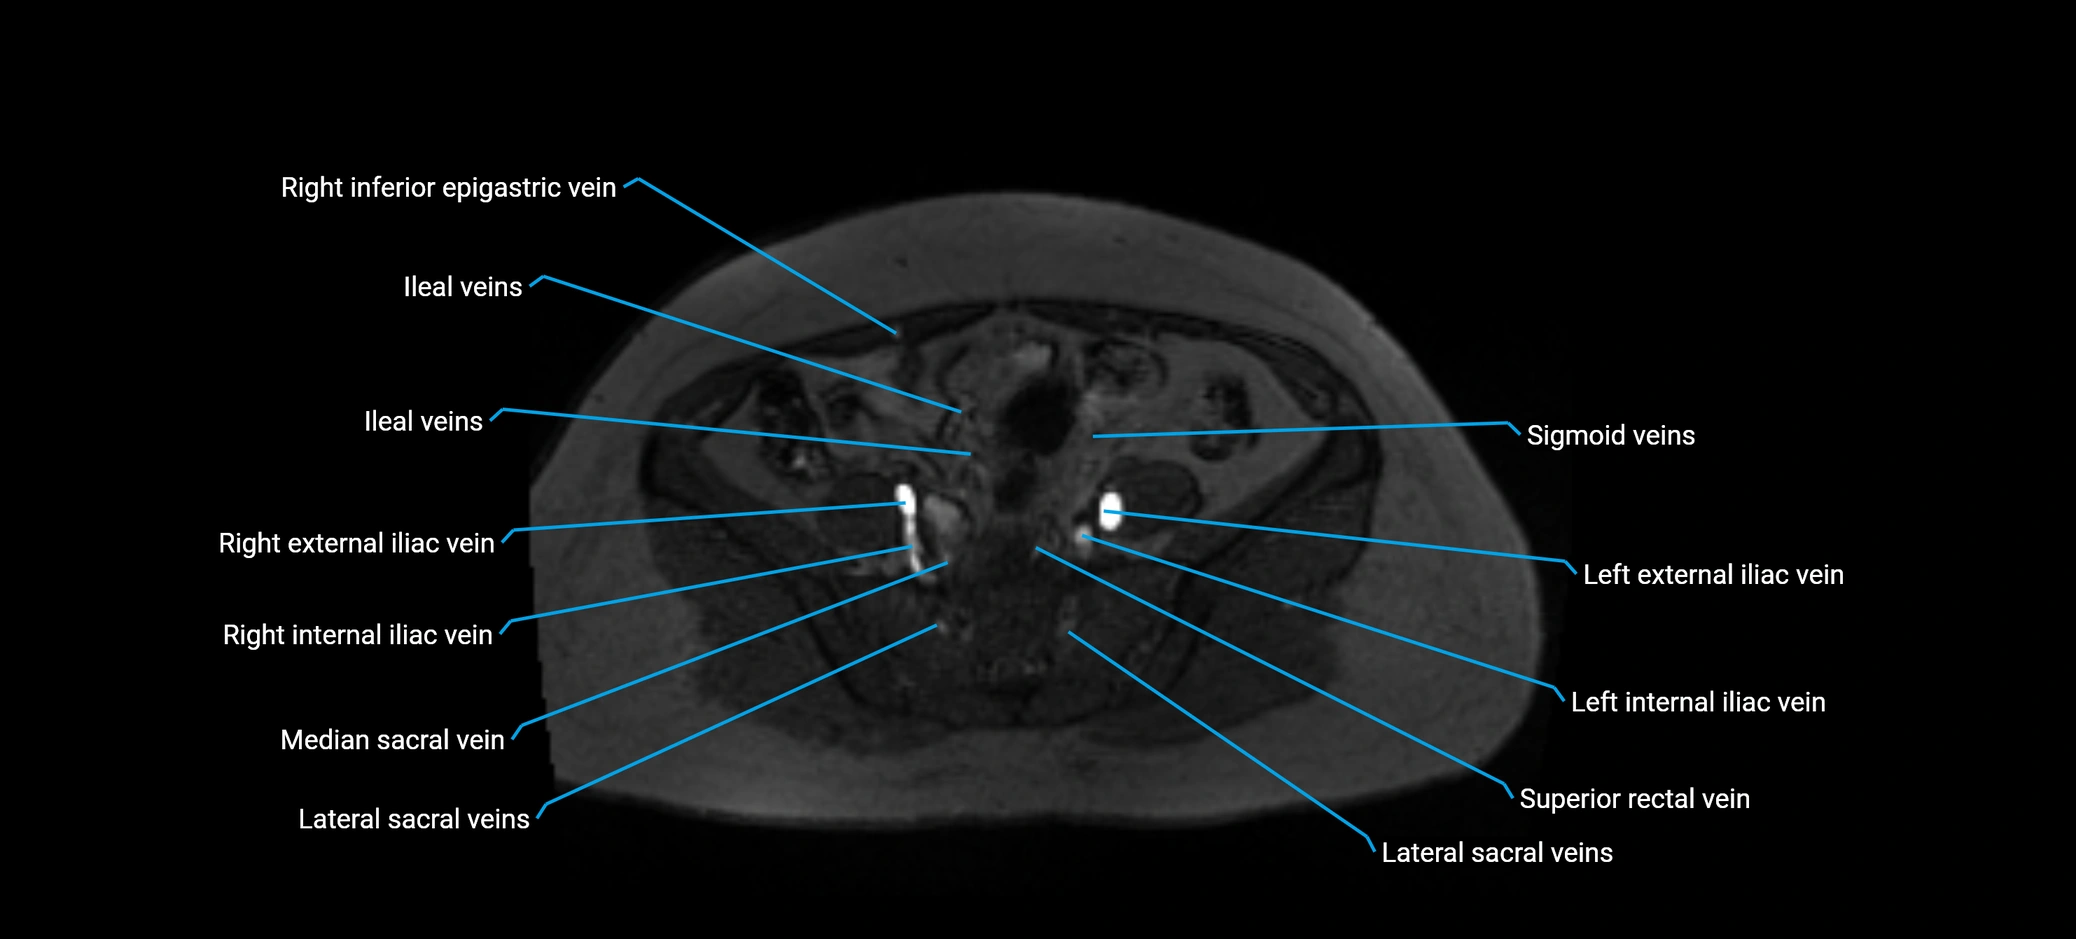

MRI image

image